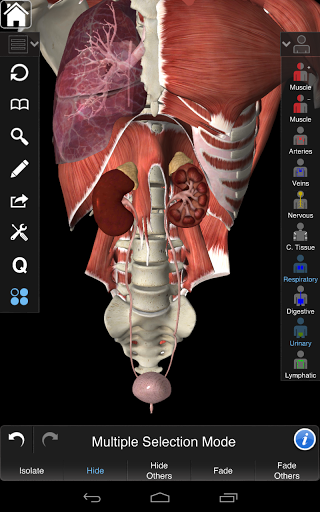

Розумна функціональність, знайдена в додатку, дозволяє користувачеві знімати шари м'язів за допомогою інструмента «скальпель». Ця програма надає користувачам можливість увімкнення / вимкнення систем без необхідності скасувати вибір окремих структур або переплутати через безліч попередньо визначених регіональних вкладок, як і інші програми.

---- Режим вибору декількох - Сховати / Зменшити / Виділити окремі або кілька структур

---- Зручний та інтуїтивно зрозумілий інтерфейс